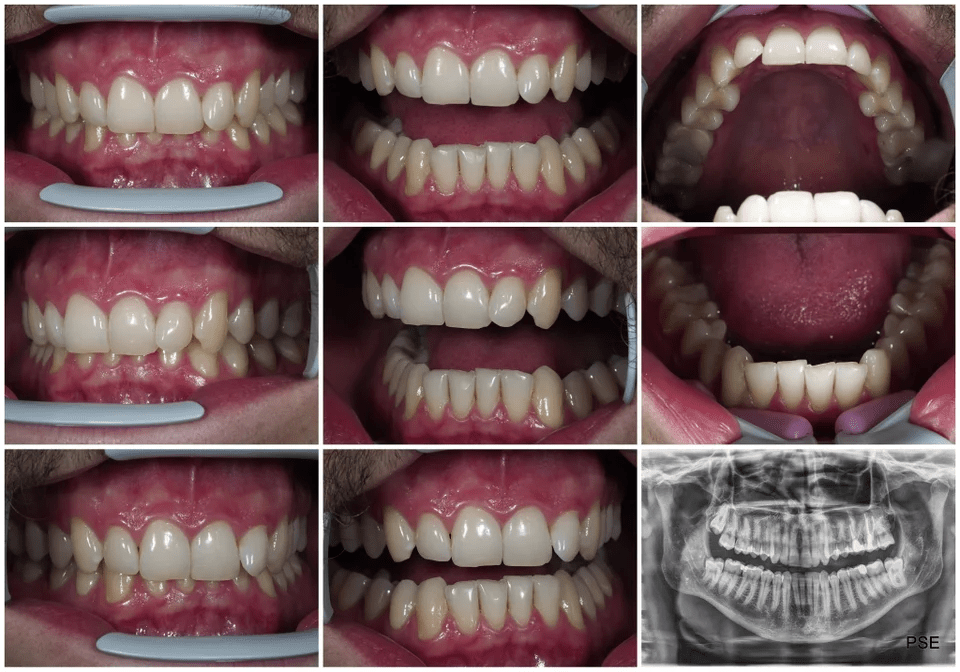

From www.zborildentalcenter.com

From www.reddit.com